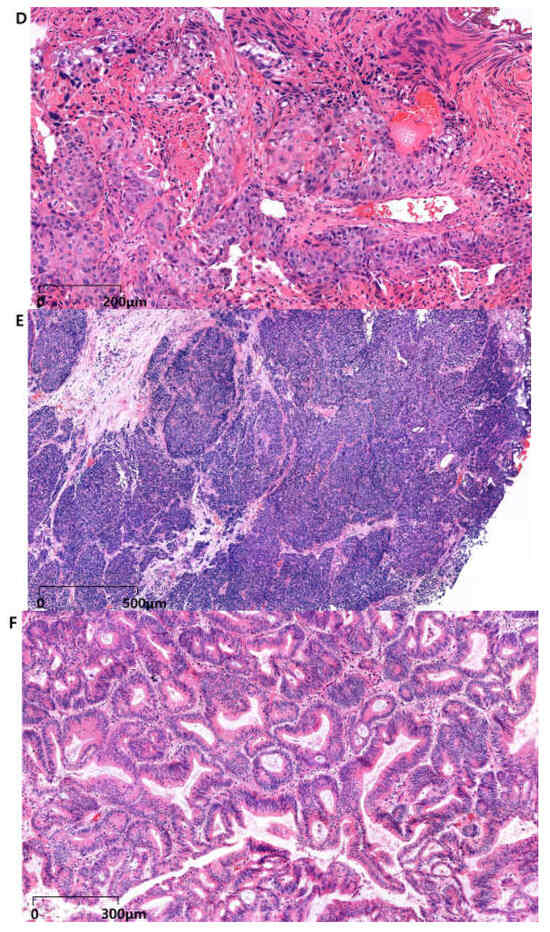

| Sarcomatoid Urothelial Carcinoma (SUC) | 0.1–0.3% of bladder tumors | - High-grade sarcomatous differentiation - Malignant spindle cells with mesenchymal phenotype - Possible differentiation into osteosarcoma, rhabdomyosarcoma, or chondrosarcoma - Mixed epithelial and mesenchymal components | - TP53, RB1, PIK3CA mutations - EGFR or FGFR alterations in basal and double-negative subtypes - High PD-L1 expression | - Highly aggressive - Approximately 50% present with metastatic disease at diagnosis - Poor prognosis | - Surgery: Radical cystectomy recommended, especially for localized disease - Chemotherapy: Neoadjuvant chemotherapy shows survival benefits; platinum-based regimens (e.g., gemcitabine and cisplatin) - Immunotherapy: Immune checkpoint inhibitors (e.g., anti-PD-1/PD-L1) show response rates of 35–40% - ADCs: Enfortumab vedotin and other ADCs under investigation | Extremely poor due to high aggressiveness and metastatic potential | - Neoadjuvant Chemotherapy: Recent meta-analyses show significant survival benefits - Immunotherapy: Promising response rates with checkpoint inhibitors - ADCs: Limited efficacy in pure SUC; ongoing trials evaluating combinations | - Heterogeneous histology complicates diagnosis - Limited treatment options - High levels of PD-L1 expression offer potential but require more research - Need for molecular profiling to guide targeted therapies | [76,77,78,79,80,81,82,83,84,85,86] |

| Squamous Cell Bladder Cancer (SCC) | 2–3% in Western countries - Higher in regions endemic with Schistosoma haematobium | - Cohesive tumor cells with keratinization and intercellular bridges - Originates from keratinizing squamous metaplasia - Similar to linitis plastica phenotype | - Loss of chromosome arm 3p - NOTCH1, TP63, and SOX2 mutations | - More prevalent in African regions due to Schistosoma infection - High propensity for local invasion - Aggressive local disease - Poor prognosis | - Surgery: Primary treatment is surgical resection (radical cystectomy) - Chemoradiotherapy: Considered when surgery is contraindicated - Chemotherapy: Platinum-based regimens show some efficacy - Immunotherapy: Immune checkpoint inhibitors show response rates of 28% in UC with SqD - ADCs: Enfortumab vedotin and sacituzumab govitecan show varying response rates depending on histologic components | Poor prognosis due to aggressive local invasion | - Chemotherapy: Variable efficacy; some response with platinum-based and taxane regimens - Immunotherapy: Moderate response rates - ADCs: Higher response rates in mixed histologies; limited efficacy in pure SCC | - Rarity leads to limited prospective clinical trial data - Diagnostic challenges due to morphological similarities with plasma cells and other SCCs - Variable response to therapies based on histologic composition - Need for targeted therapies specific to molecular drivers | [87,88,89,90,91,92,93,94,95,96,97,98,99,100,101,102,103,104] |

| Adenocarcinoma (Non-Urachal and Urachal [UrCA] Subtypes) | ~0.8% of bladder cancers UrCA: ~10% of BAC | - Non-Urachal: Various morphological patterns (papillary, nodular, flat, and ulcerative) - Well to moderately differentiated glandular morphology - Resembles colorectal adenocarcinoma - UrCA: Localizes to dome and anterior bladder wall - Enteric, mucinous, signet ring cell, and mixed subtypes | - Non-Urachal: KRAS, MYC, FLT3, and TERT mutations - UrCA: SMAD4, GNAS mutations; lower frequency of TERT and RB1 than that of non-urachal - Shared mutations with colorectal cancer (e.g., TP53, KRAS, and APC) | - Non-Urachal: Prognosis is worse than that ofUrCA - UrCA: Presents at later stages because of anatomical position - Higher propensity for peritoneal metastasis - Typically presents at muscle-invasive and advanced stages - Younger patients with UrCA have better survival outcomes than those with non-urachal | - Surgery: Radical cystectomy for localized disease - Chemotherapy: Platinum-based regimens (e.g., FOLFOX, CAPOX) similar to colorectal cancer - Targeted Therapy: Potential use of therapies effective in colorectal cancer (e.g., EGFR inhibitors) - Immunotherapy: Limited efficacy due to low tumor mutation burden and reduced PD-L1 expression - ADCs: Enfortumab vedotin shows limited efficacy in pure adenocarcinoma but works better in mixed histologies | Generally poor, especially for non-urachal subtypes UrCA has relatively better outcomes due to earlier detection and less aggressive progression | - Chemotherapy: Variable response rates; some efficacy with colorectal-like regimens - Immunotherapy: Heterogeneous responses, generally lower efficacy due to molecular characteristics - ADCs: Better responses in mixed histologies with UC components - Targeted Therapies: Potential benefits from colorectal cancer-targeted approaches | - Extremely rare, limiting prospective clinical trial data - Diagnostic challenges due to morphological similarities with colorectal adenocarcinoma - Need for molecular profiling to guide treatment - Variability in treatment responses based on histologic and molecular subtypes | [112,113,114,115,116,117,118,119,120,121,122,123,124,125,126,127,128] |